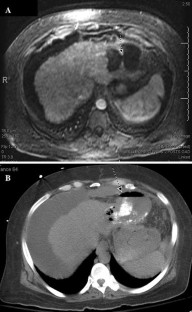

Fig. 2